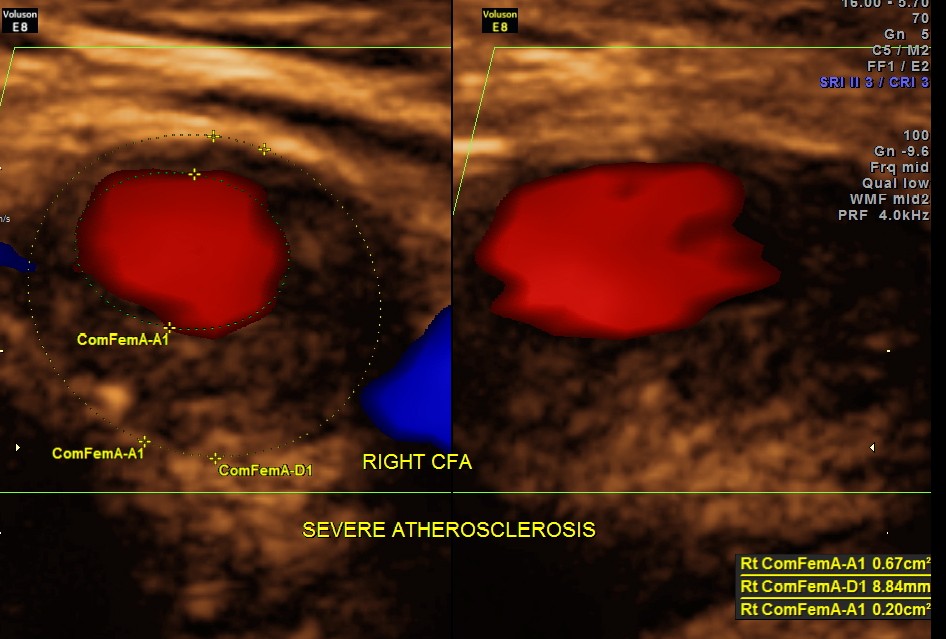

Rt Common Femoral artery showed nearly 70 % obstruction.

EXTENSIVE ATHEROSCLEROTIC OBSTRUCTIVE DISEASE OF THE LOWER LIMB ARTERIES WAS SEEN WITH THE CHANGES IN THE RIGHT COMMON FEMORAL ARTERY BEING MORE THAN THE LEFT CFA.